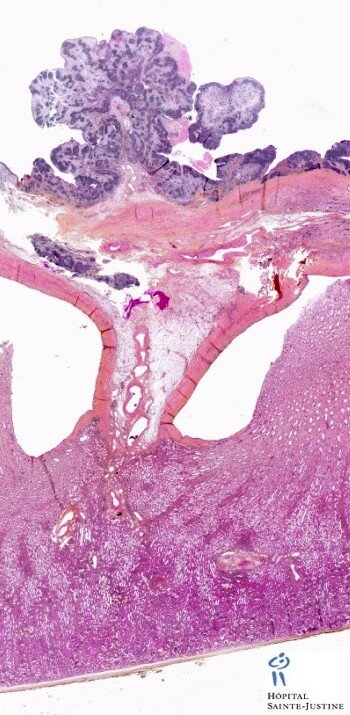

botryoid Wilms tumor

Wilms tumor

(nephroblastoma)